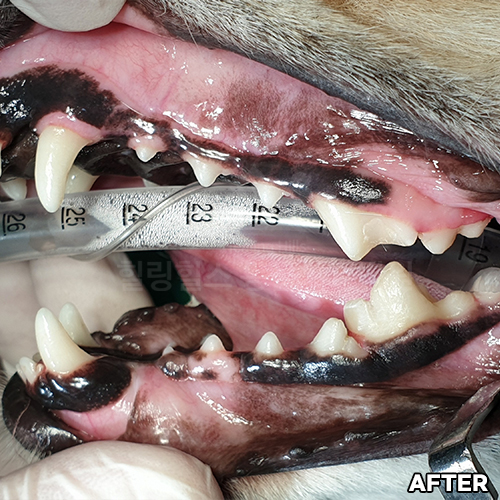

강아지스케일링 및 치주치료! - 자기치아살리는 힐링힐스동물치과 -